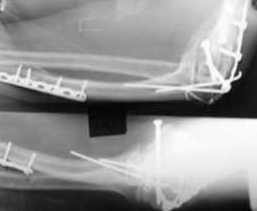

Подскажите пожалуйста, как можно в дальнейшем этому больному помочь. В марте первая

операция, пришлось оперировать на 16 сутки в виду инфицированных садин и анемии. Заживление

первичным натяжением, ранняя разработка после операции, а через 2 нед болевой синдром,и

постепенно движения в локтевом суставе ограничились до полного анкилоза. Повторно через 4

месяца вторая операция - артролиз, удаление оссификатов, удаление фиксаторов,

реостеосинтез этой же реконструкционной пластиной и винтом. Интраоперационно после

удаления оссификатов и фиксаторов обнаружил, что переломы не сросшиеся, поэтому пришлось

синтезировать заново. Зажила рана первично, объем движений в локтевом суставе сгибание 70,

разгибание160, ротационные движения востановились полностью, вроде бы успокоились.

Опять постепенно в течении 8 нед после повторной операции постепенно движения ограничились

до 80 - 110, на снимке оссификат. Снимки во вложении, буду рад Вашим советам. Спасибо!